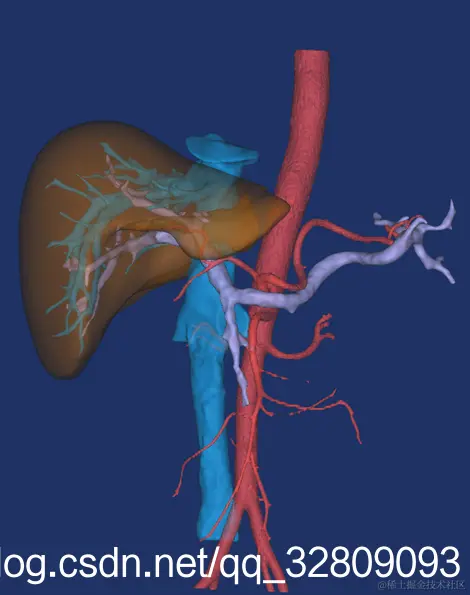

最后建模出来的效果:

正面图(肝脏+动脉+门静脉+腔静脉)                                反面图                                                          透视图

三种视图: